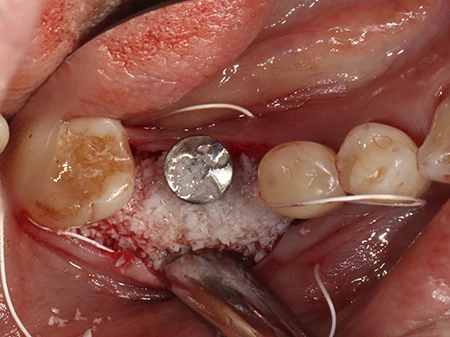

移植した骨に軟組織が入り込まないようにコラーゲンの膜で保護します。

キャップが歯ぐきから少しでた状態で縫合して終了です。骨の移植をした場合は2〜3ヶ月ほど待って型取りを行います。